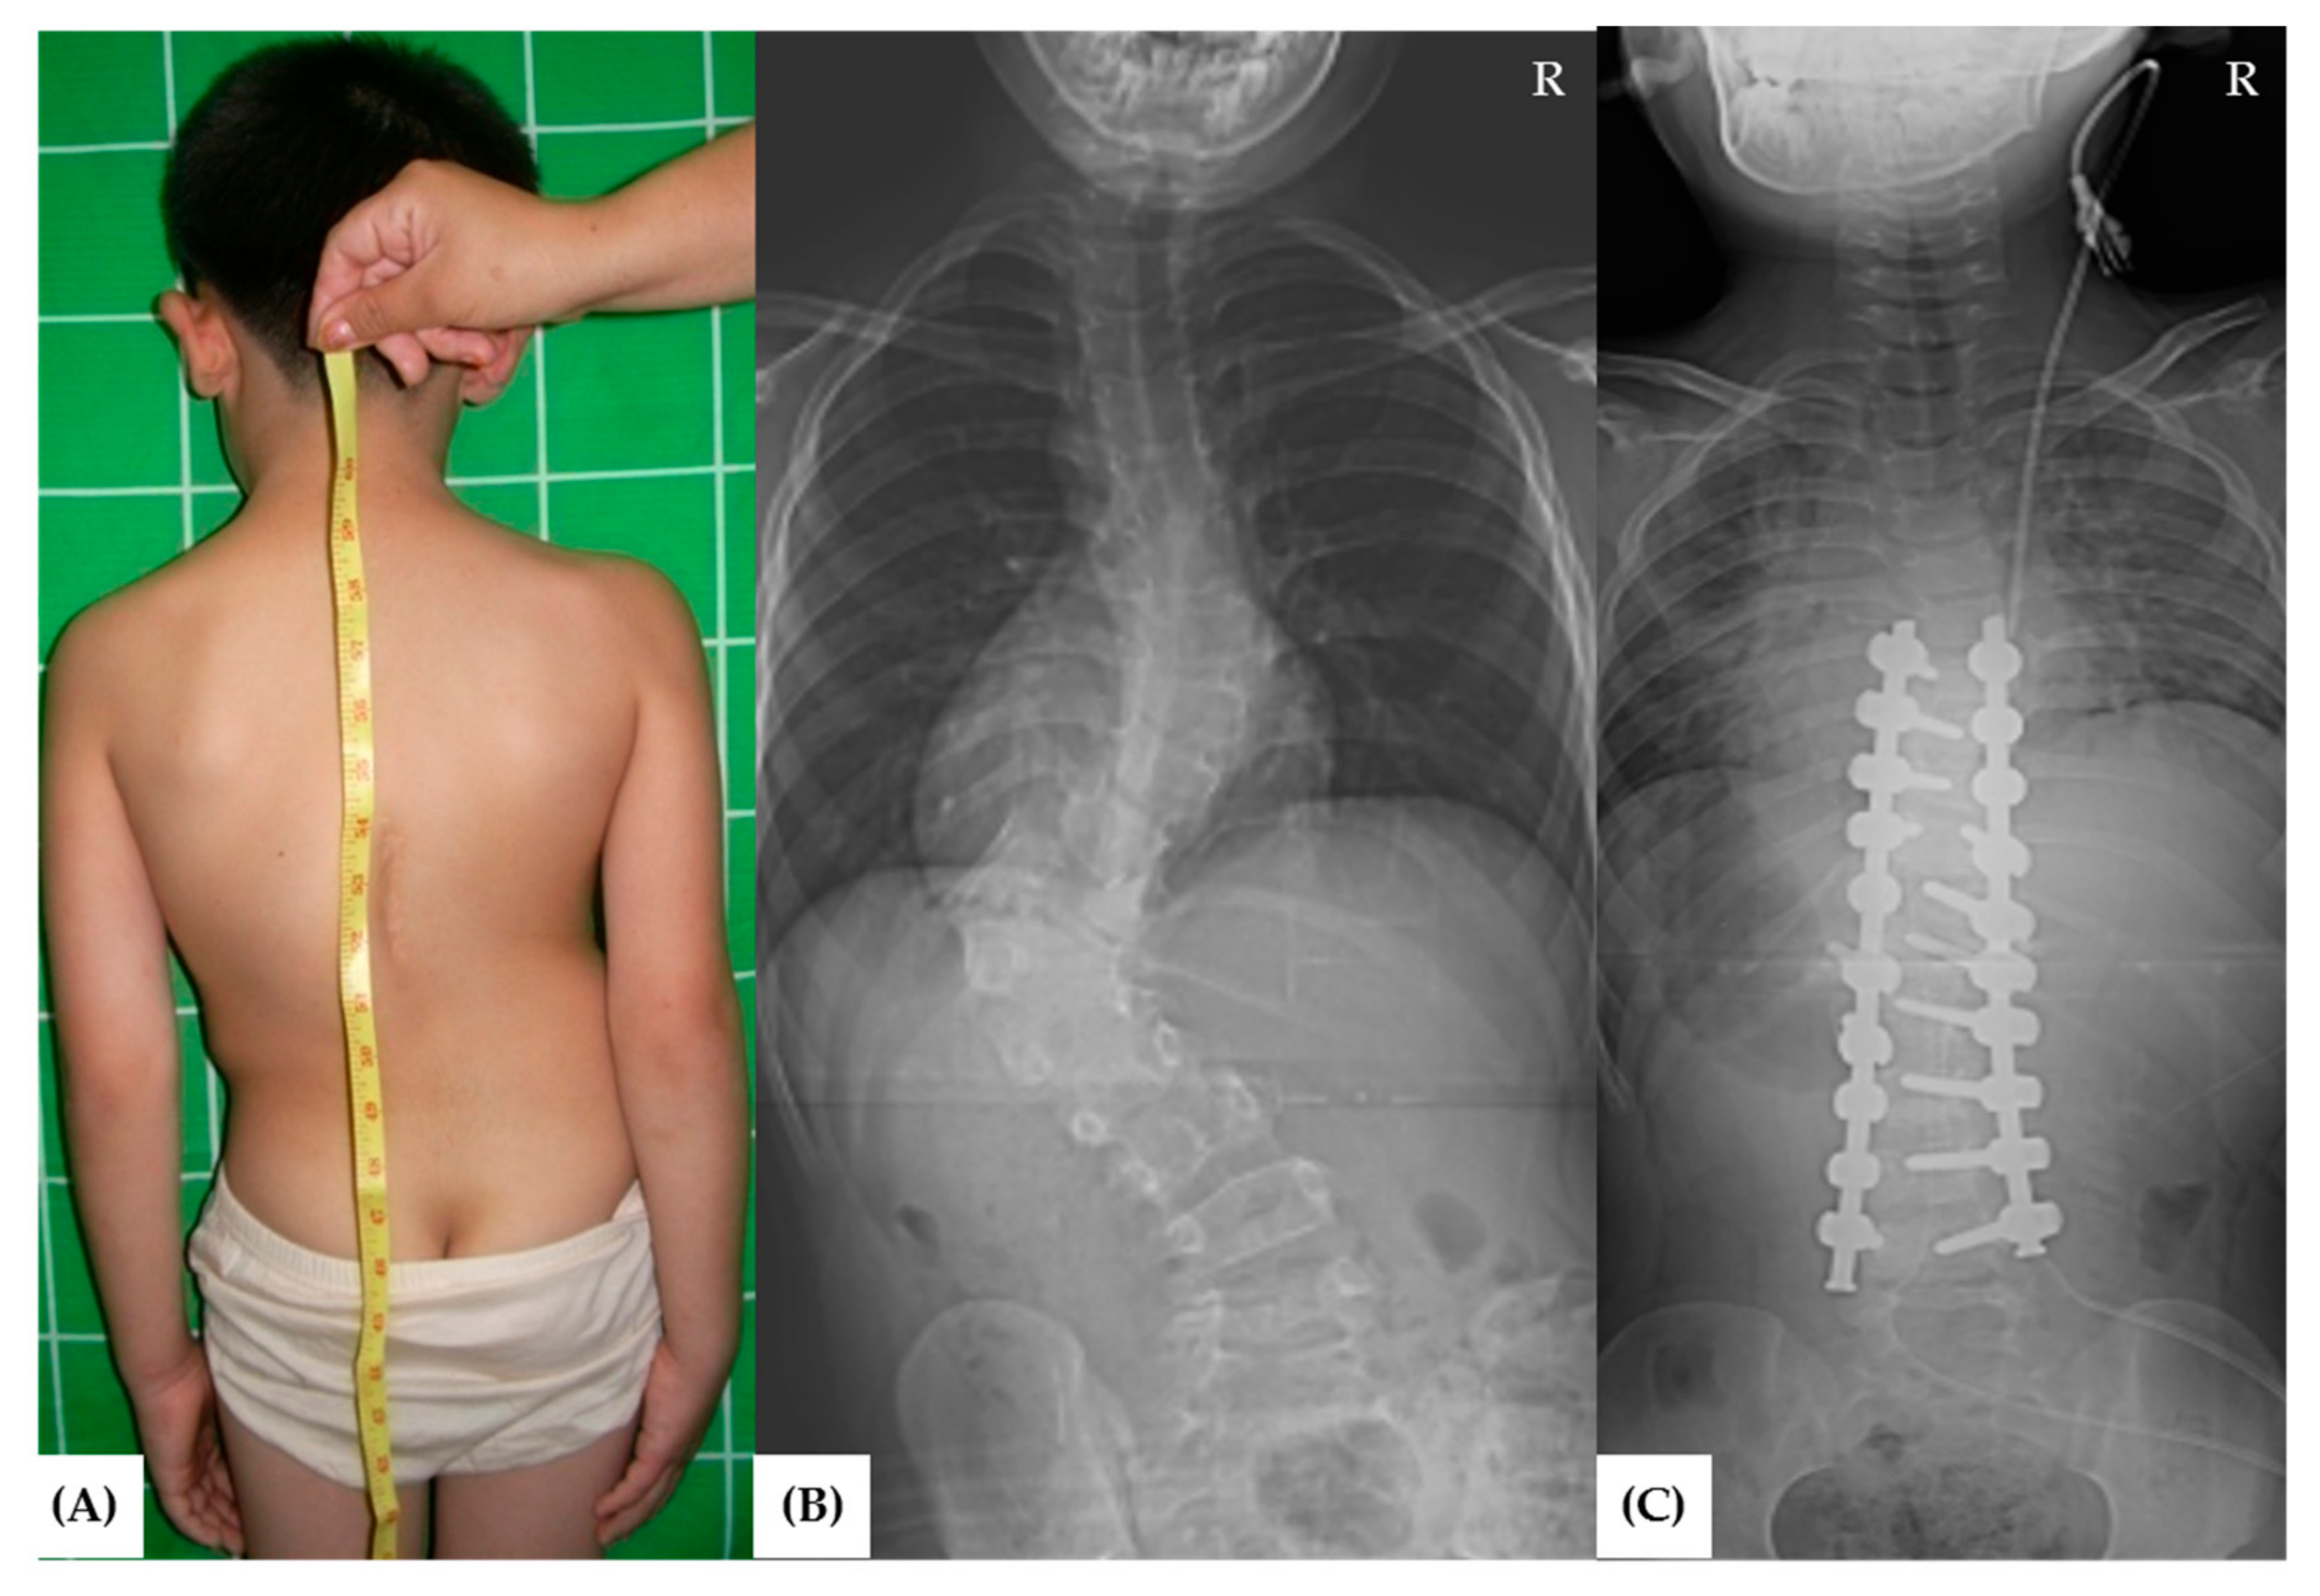

- Chang, D.G.; Suk, S.-I.; Kim, J.-H.; Ha, K.-Y.; Na, K.-H.; Lee, J.-H. Surgical outcomes by age at the time of surgery in the treatment of congenital scoliosis in children under age 10. Spine J. 2015, 15, 1783–1795. [Google Scholar] [CrossRef]

- Yang, J.H.; Chang, D.G.; Suh, S.W.; Kim, W.; Park, J. Clinical and radiological outcomes of hemivertebra resection for congenital scoliosis in children under age 10 years: More than 5-year follow-up. Medicine 2020, 99, e21720. [Google Scholar] [CrossRef]

- Chang, D.G.; Yang, J.H.; Lee, J.H.; Kim, J.H.; Suh, S.W.; Ha, K.Y.; Suk, S.I. Congenital scoliosis treated with posterior vertebral column resection in patients younger than 18 years: Longer than 10-year follow-up. J. Neurosurg. Spine 2016, 25, 225–233. [Google Scholar] [CrossRef] [Green Version]